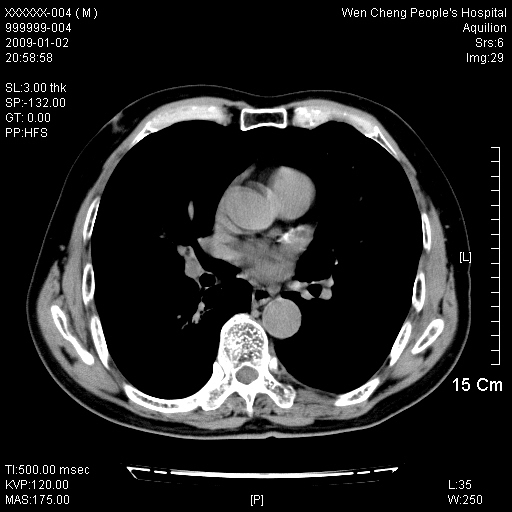

男性,73岁,有慢支病史,肿瘤系列标志物检验正常,血沉及血常规正常

右肺下叶背段小片状 磨玻璃样模糊影,内见血管及含气支气管像,支气管管壁增厚。考虑:慢性炎症!

1)不排除右肺下叶周围型肺癌可能;建议追踪复查。2)左右冠状动脉钙化。

右肺下叶背段小片状 实性与磨玻璃样影,内见血管及含气支气管像,支气管管壁增厚,边缘见长毛刺影。考虑:慢性炎症或肿瘤!建议抗炎治疗复查,密切观察随访!

右肺下叶片团状影内见扩张的含气支气管和支气管管壁增厚,其周有磨玻璃样模糊影和长毛刺。考虑慢性炎症可能性大。

2、右肺下叶片团状影内见扩张的含气支气管和支气管管壁增厚,其周有磨玻璃样模糊影和长毛刺。考虑周围型肺ca可能,结核不排。

高度提示细支气管肺泡癌,建议抗炎治疗半月观察病灶变化,如无明显改变,建议立即手术治疗.